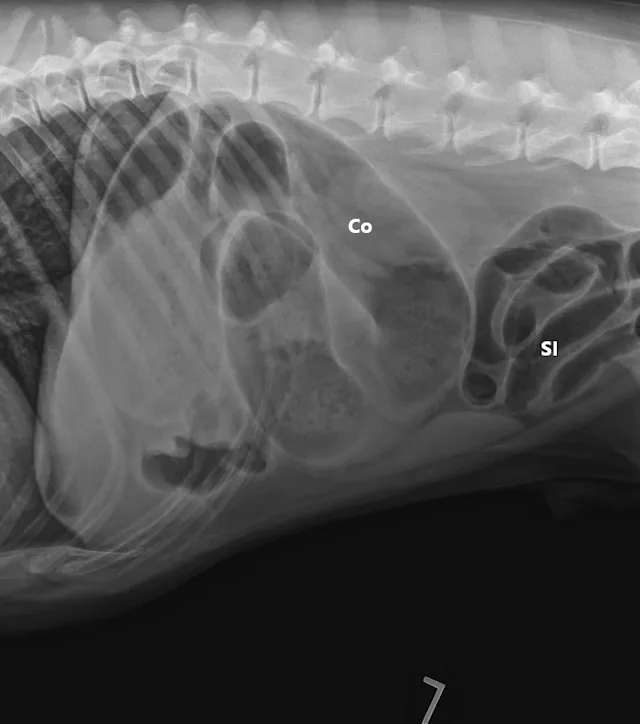

Three-view abdominal radiographs revealed a single bowel loop markedly dilated with gas and amorphous material in the cranial abdomen thought to represent the colon due to its unusual position (ie, could not be tracked from caudal to cranial aspect on lateral radiograph; Figure 1). The small intestines were displaced caudally with no evidence of ileus (ie, gas filled but normal and uniform in diameter), and the descending colon was not fully visualized.

FIGURE 1A

Right lateral (A), left lateral (B), and ventrodorsal (C) abdominal radiographs demonstrating marked dilation of a single bowel loop with gas and amorphous material in the right cranial abdomen, suspected to be the colon (arrows). Caudal displacement of the small intestines (SI) can also be seen. The descending colon (Co) is poorly visualized.